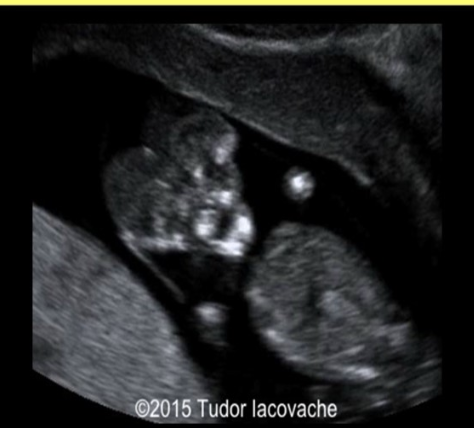

a) fetal ascites + skin edema of the abd

b) fetal ascites + pleural effusions

c) skin edema of fetal abd

d) fetal ascites